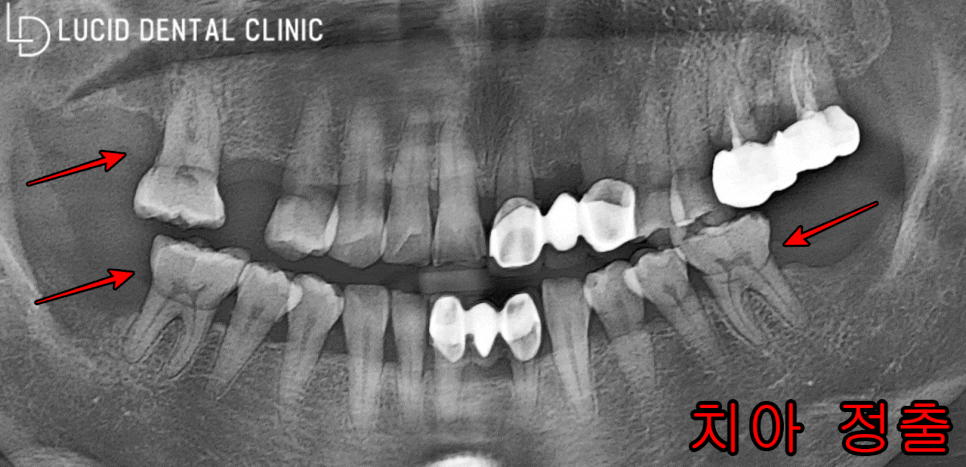

파노라마 엑스레이를 통해

-

치아 정출

발치 후 빈 곳

두 가지 문제점을 발견했습니다.

결국, 발치하고 제대로 처치받지 않아

1번 치아 정출까지 나타나고 만 것인데요

이는 자연치가 조금씩 스스로 움직이려는

특징이 있기에 나타나게 되는 것입니다.